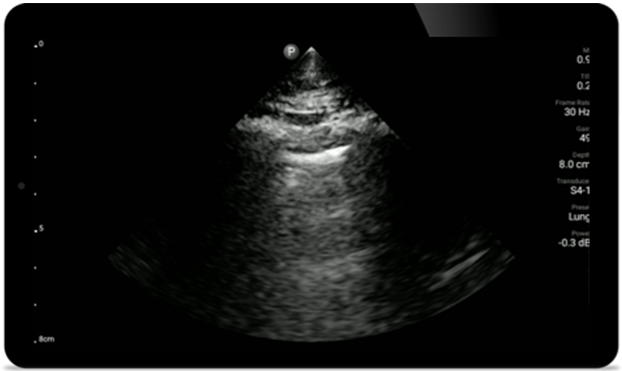

Use Lumify for airway and pulmonary assessment

Lumify POCUS solutions can help you detect the endotracheal tube within the trachea, assist in emergent cricothyrotomy procedures, diagnose pleural effusion and interstitial alveolar diseases.

Pulmonary assessment